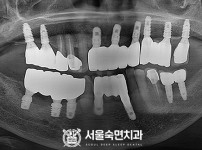

임플란트-전후사진1